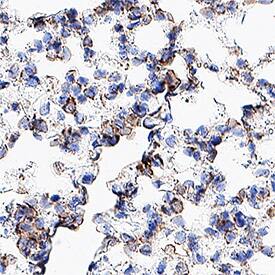

Detection of CD11c in Mouse Lung.

CD11c was detected in immersion fixed paraffin-embedded sections of mouse lung using Rat Anti-Mouse CD11c Monoclonal Antibody (Catalog # MAB6950) at 5 µg/ml for 1 hour at room temperature followed by incubation with the Anti-Rat IgG VisUCyte™ HRP Polymer Antibody (Catalog # VC005). Before incubation with the primary antibody, tissue was subjected to heat-induced epitope retrieval using VisUCyte Antigen Retrieval Reagent-Basic (Catalog # VCTS021). Tissue was stained using DAB (brown) and counterstained with hematoxylin (blue). Specific staining was localized to macrophages. View our protocol for Chromogenic IHC Staining of Paraffin-embedded Tissue Sections.